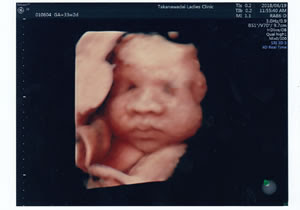

3d 4dエコー 高輪台レディースクリニック 港区の産科 婦人科

4dエコー 兵庫県西宮市 宝塚市の産婦人科 サンタクルス

赤ちゃんの表情もくっきり 最新3d 4dエコー検査 恵比寿の産婦人科 広尾レディース 妊婦健診 子宮がん検診 ブライダルチェック

3d 4dエコー検査 和歌山市のやましたレディース マタニティクリニック